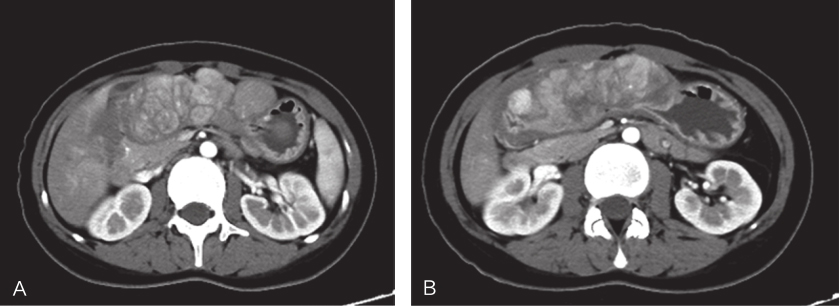

2015年12月复查腹部CT示:①胃多发肿块,胃GIST可能,较3个月前肿瘤大小无明显变化;②肝内稍低密度影,考虑肝脏多发血管瘤(图2)。当地医生考虑患者为胃GIST靶向治疗后疾病稳定,决定维持当前治疗方案。2016年3月19日复查腹部CT示:①胃窦、胃小弯、侧壁及肝胃间区多发富血供肿块,考虑为胃肠间质瘤;②盆腔左侧团块灶,考虑为左侧卵巢肿瘤;③肝内稍低密度影,考虑肝脏多发血管瘤。肿瘤大小较3个月前明显增大并出现肝胃间隙转移,患者为求进一步治疗,遂前往华中科技大学同济医学院附属协和医院胃肠间质瘤专病门诊就诊,门诊以“(胃)胃肠间质瘤靶向治疗后,肝脏多发占位,左侧卵巢占位”收入。

图2服药3个月复查CT

A、B.横断位;C.冠状位